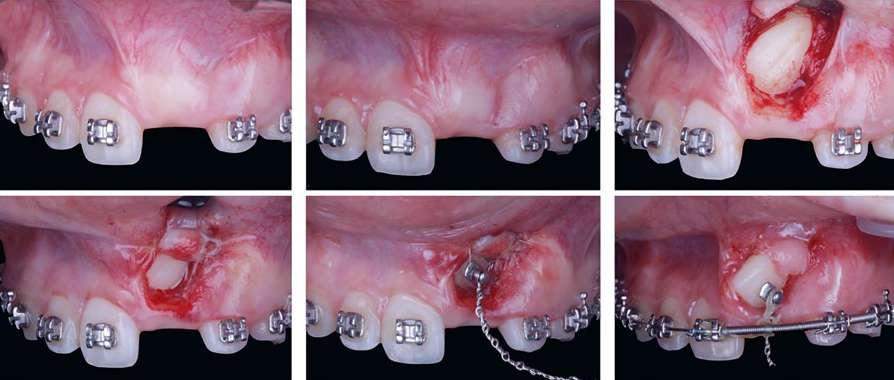

Figura 1. Diagnóstico clínico y radiográfico de un caso de inclusión de caninos. a) Cementado de brackets; b) Corte coronal del CBCT: inclusión por palatino de 1.3 y 2.3; c) Arcada con espacio preparado para caninos mediante coils abiertos; d) Radiografía panorámica: pronóstico

2.3 según

de tracción favorable del 1.3 y desfavorable del

Ericson y Kurol en relación a: ángulo alfa, posición mesio-distal, altura del canino respecto al LAC del lateral y grado de erupción del canino.

Actualmente, la tomografía computarizada de haz cónico (CBCT por sus siglas en inglés: Cone Beam Computed Tomography) y la reconstrucción 3D nos permiten ver con más claridad la posición del canino y su relación con estructuras adyacentes (Alqerban y cols. 2009). En el año 2000 se desarrolló un nuevo método para evaluar, a partir del CBCT, la dificultad prevista para posicionar un canino incluido, el índice KPG. Este índice clasifica la posición del canino en función de su distancia de la norma, dando un número en una escala de 0 a 5 tanto para la

cúspide como para la punta de la raíz. La suma de las seis puntuaciones obtenidas evalúa la dificultad prevista del canino (Dalessandri y cols. 2013).

La impactación de los caninos permanentes superiores es la segunda forma más común de impactación de dientes después de los terceros molares, siendo dos veces más común en mujeres que en hombres (Becker y cols. 2015). La erupción del canino permanente suele ocurrir alrededor de los 11 años, por lo que la sospecha de su inclusión suele comenzar a los 14-15 años. La impactación palatina es más frecuente que la impactación vestibular (3 veces) y la unilateral más común que la bilateral (Chung y cols. 2011). La etiología es multifactorial y podría estar relacionada, entre otras causas, con discrepancias en el tamaño del diente y la longitud de arcada, genética, erupción tardía, deficiencia transversal del maxilar, migración dentaria, traumatismo en el maxilar o agenesia/anomalía de posición en incisivo lateral (Martínez Madero y cols. 2022; McConnell y cols. 1996).

Clínicamente, los caninos incluidos se caracterizan por la erupción retardada del canino permanente, la erupción asimétrica de ambos caninos, la ausencia de protuberancia canina en el fondo de vestíbulo o presencia de protuberancia palatina en la región canina, el retraso en la erupción o migración distal de incisivos laterales permanentes, la retención prolongada de canino temporal sin movilidad y pérdida de vitalidad o el aumento de movilidad de incisivos permanentes (Mason y cols. 2001).

El diagnóstico radiográfico en dos dimensiones de un canino incluido se lleva a cabo mediante la radiografía periapical con la técnica de Clark y la radio-

grafía panorámica. En esta última, se han estudiado diferentes variables radiográficas para la evaluación del pronóstico de los caninos incluidos. En 1988, Ericsol y Kurol establecieron cinco sectores según los ejes longitudinales del incisivo central y lateral y líneas paralelas que pasan por los puntos de contacto desde el incisivo central al primer premolar. Así, describieron métodos para conocer la posición mesio-distal de la corona del canino, la inclinación del mismo respecto a la línea media y al incisivo lateral y el grado de predictibilidad de la erupción del canino, siendo un peor pronóstico cuando más a mesial se encuentre su cúspide. Se determinó también el ángulo alfa definido por el eje longitudinal del canino con la línea media y se consideró un valor normal, con buena predictibilidad de erupción, un ángulo de 25º (Ericson y Kurol 1986, 1988) (Figura 1). McSherry (1996) describió “la regla vertical de los tercios”. Con ello, se puede esperar un buen pronóstico si la punta de la cúspide canina está al nivel de la unión amelocementaria del incisivo adyacente, mientras que un canino con mal pronóstico para la alineación sería aquel en el que la punta de la cúspide estuviera contra el tercio apical del incisivo adyacente (McSherry, 1998). Pitt, en el año 2005, evaluó con una puntuación de 1 a 4 el grado de dificultad de alineación del canino incluido en la arcada dentaria teniendo en cuenta su altura vertical, posición horizontal respecto al incisivo lateral, posición vestíbulo-palatina y la edad del paciente (Pitt y cols. 2006).